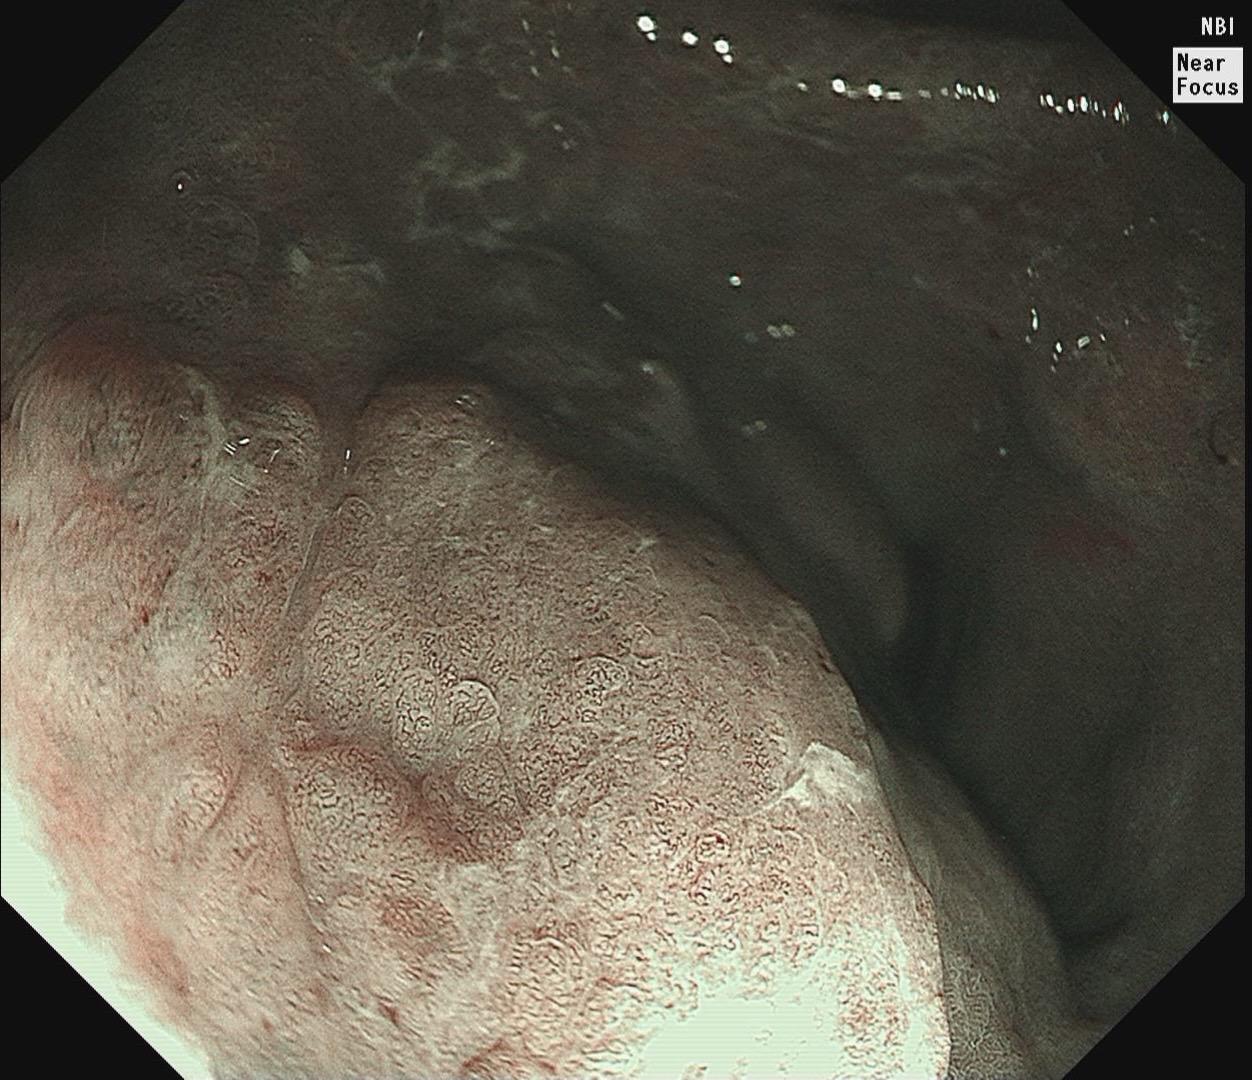

男,61岁,胃巨大褪色调病变。答案在最后一张图片,你猜对了吗? 患者因上腹部饱胀行胃镜检查,Hp阴性背景,胃窦至贲门下见一巨大褪色调病变,边界清晰,病变相对表浅,未见明显溃疡及隆起,胃壁较柔软,充气顺应性佳,予多点活检确诊,拟外科手术行全胃切除。做这么多年胃镜,还是第一次遇到这样的……